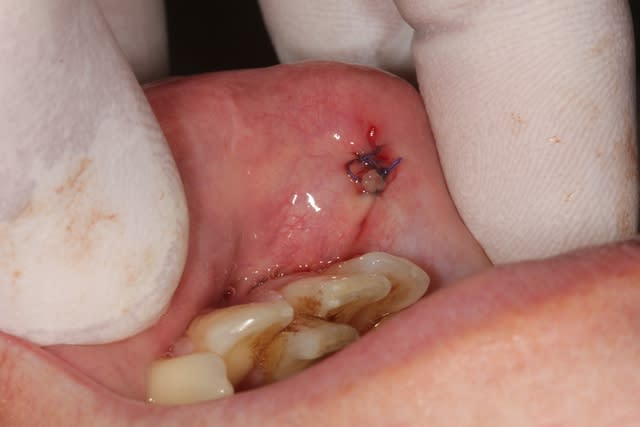

j'ai réalisé une exerèse d'un petit "fibrome" au niveau de la partie muqueuse de la lèvre mandibulaire, avec l'accord du dermato qui a vu les photos.

Dsc 0853 o2u5mi - Eugenol

Dsc 0855 vczury - Eugenol

Dsc 0856 zsy2pv - Eugenol

Dsc 0857 gmhyjs - Eugenol